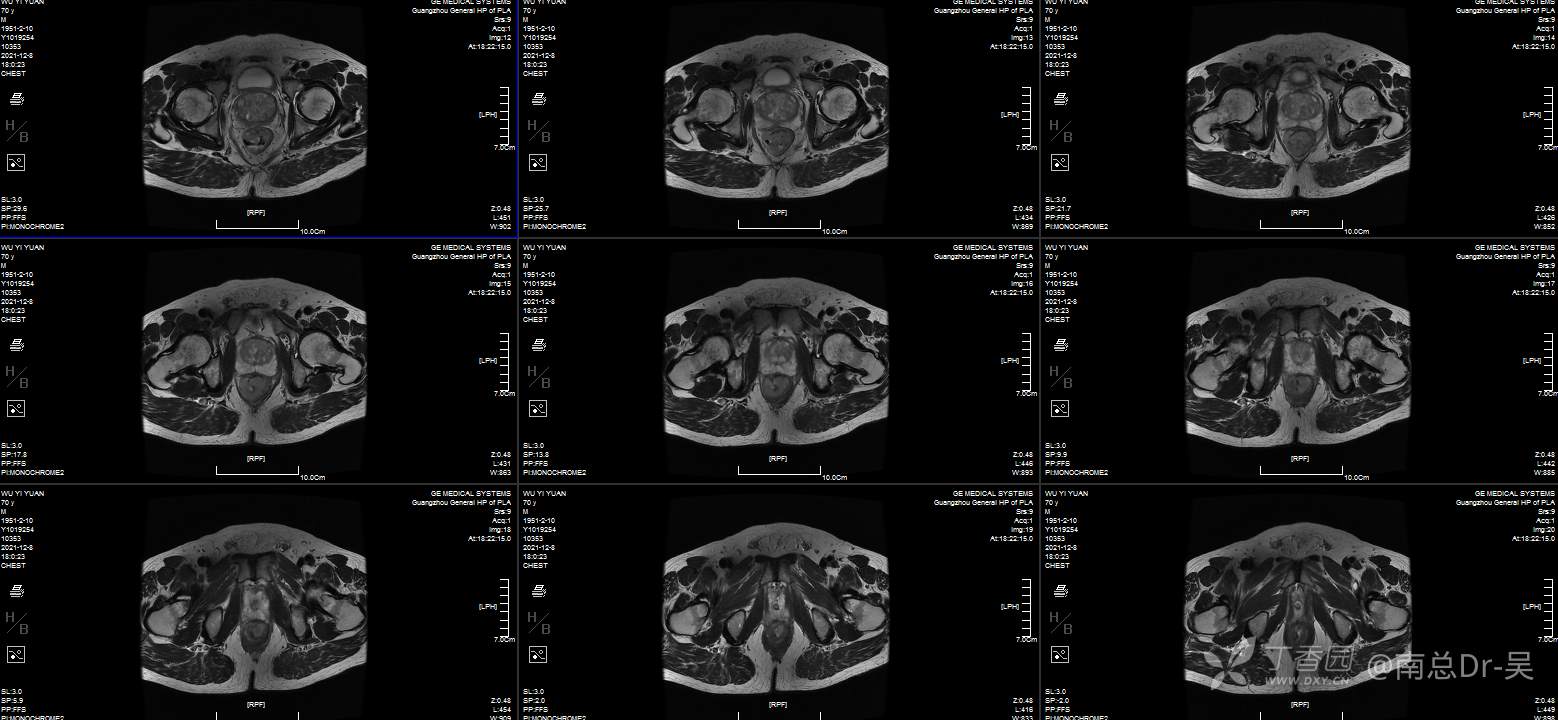

男性患者,81岁,诊断为:超低位直肠癌。肠镜提示距肛门2cm直肠占位,病理:中分化腺癌。患者本人有着强烈的保肛愿望,且评估该患者术前肛门功能良好,因此如何实施高质量的保肛手术是值得关注的问题。